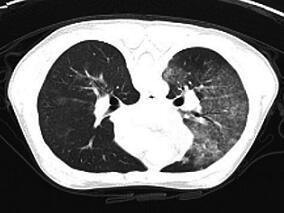

1小时条评论72岁老奶奶,因咳嗽、痰中带血伴活动后呼吸困难4个月,加重伴胸痛2天入院。据悉,该老奶奶吸烟史50年,每日约15支,会是肺癌吗? 【病情介绍】 患者女性,72岁,因咳嗽、痰中带血伴活动后呼吸困难4个月,加重伴胸痛2天于2011年8月2日住入我院呼吸内科。 患者4个月...

1小时条评论63岁男性,反复咳嗽、气促4个月,加重伴血丝痰2个月,在当地医院先后以上呼吸道感染、肺炎给予治疗,无明显好转,并且逐渐加重。该患者影像学检查结果具有极大的迷惑性,最终经过病理获得诊断。 【病情介绍】 患者男性,63岁,广州花都人,船员,现已退休,因反复...